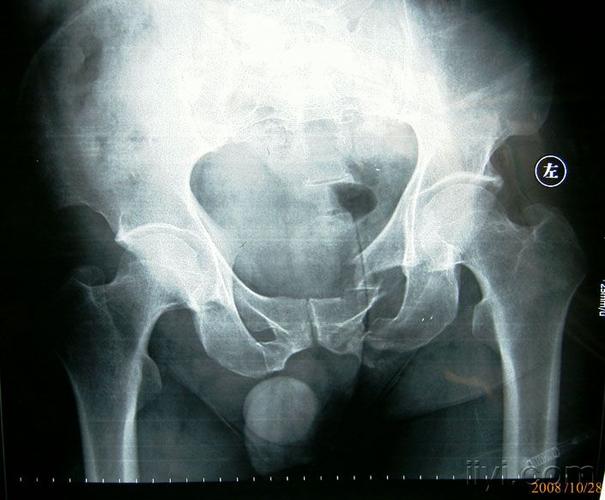

左侧坐骨支骨折图片

左侧坐骨支骨折图片,坐骨支骨图片

男,49岁,骨盆,双侧耻骨坐骨支骨折!